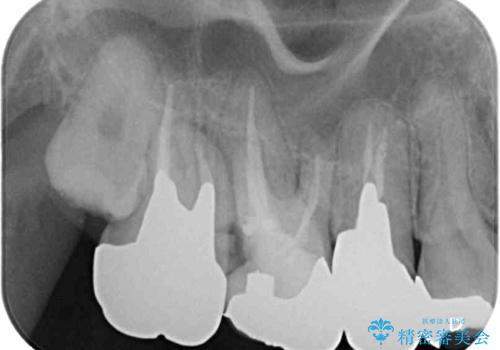

- ものが挟まるとのことで来院された患者様です。

一度は治療せずに放置していましたが、1年後のメインテナンスの際に悪化していることが分かったことから、補綴治療を行うこととしました。

神経を抜いてある歯はむし歯が進行しても痛みを感じることがないため、気がついたときには著しくむし歯が進行している可能性があります。

早めの対応とすることで、抜歯を回避できることはもちろん、外科処置などの本来必要のない処置を行わずに対処することができました。